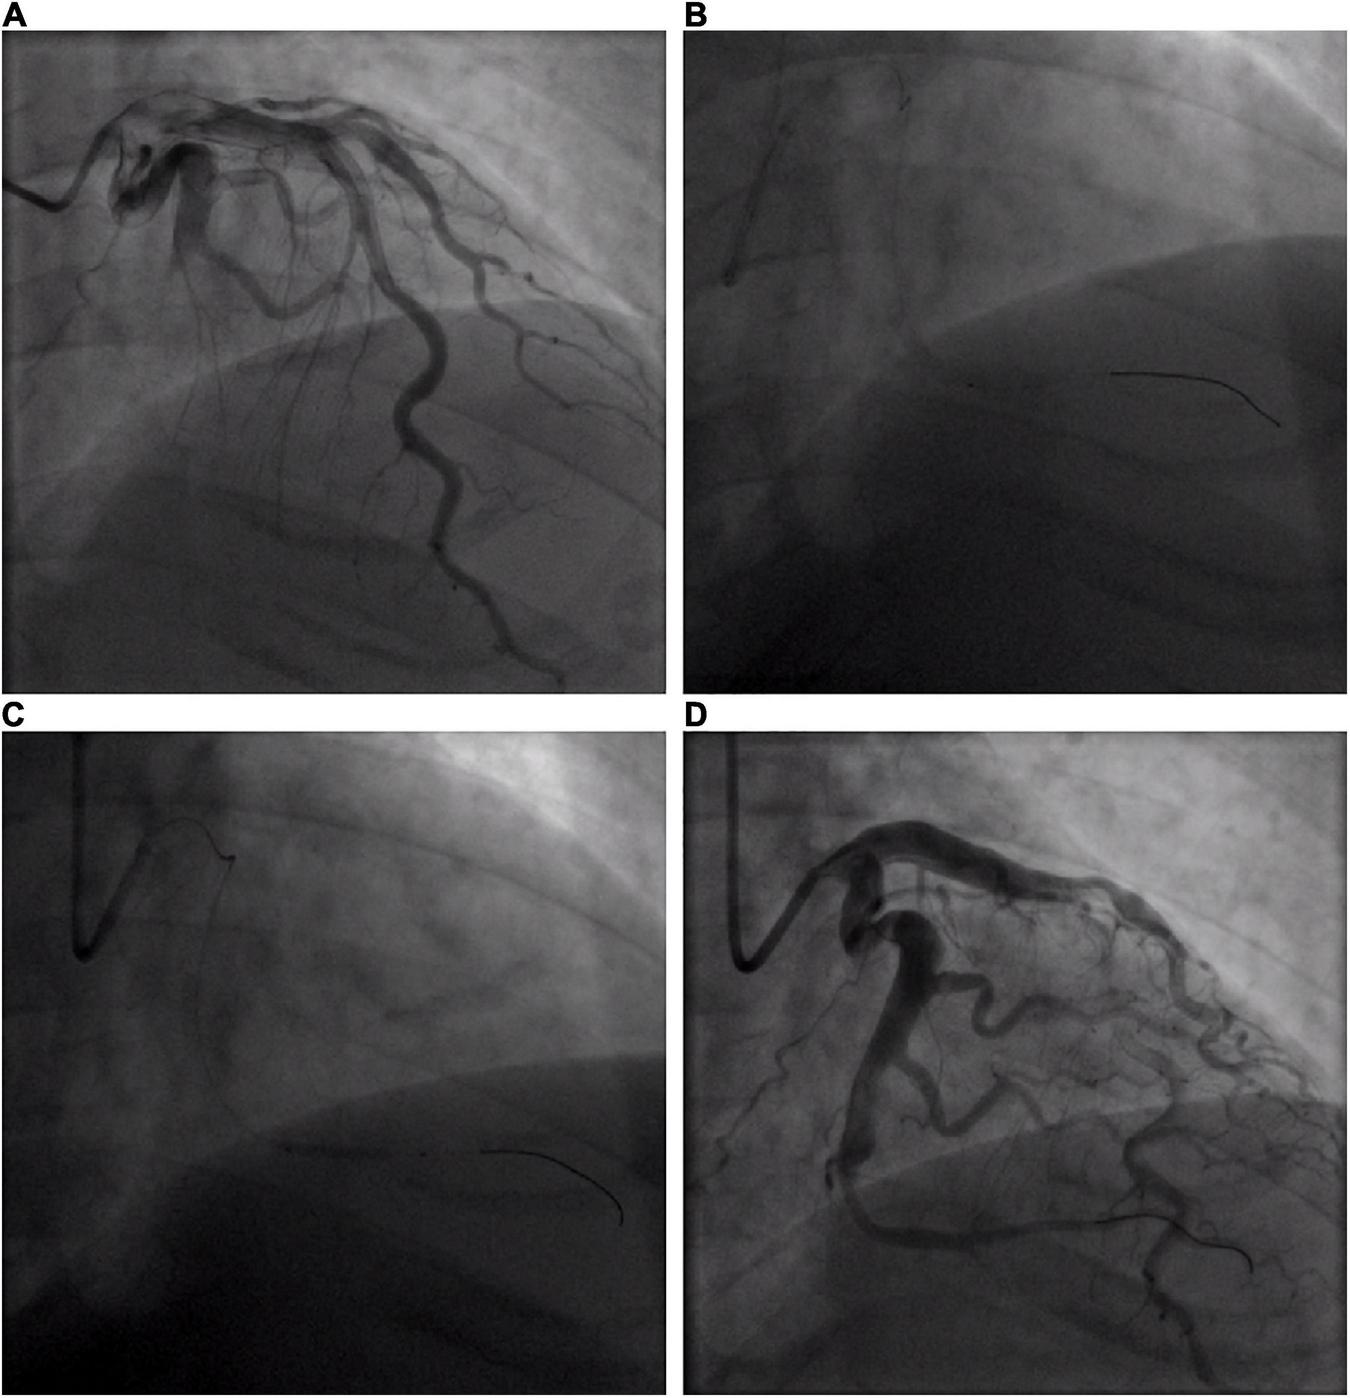

FIGURE 2

Coronary angiogram of acute circumflex artery occlusion. (A) Basal angiogram showing total occlusion of the left the circumflex artery (LCX) distal segment with thrombus image. The arrow shows the occlusion. (B) Procedure of intracoronary artery retrograde thrombolysis (ICART) through the cut balloon. The distal thrombus was gradually dissolved. The fine arrow shows the tip of the cut balloon, and the coarse arrow indicates the thrombolytic agent with contrast agent to fill the occluded lumen. (C) The distal end of the LCX was dilated up to 5 atm with a 2 mm × 20 mm compliant balloon. (D) Revascularization was achieved at the distal end of the LCX without stent implantation.

A 32-year-old young man was transferred to the emergency department with sudden chest pain lasting for 80 min. He has had high blood pressure for 4 years but on no medication, and had a blood pressure of 174/113 mmHg and a pulse rate of 78 beats per minute. Electrocardiography showed ST-segment elevations in leads II, III, aVF, V3R, V4R, and V5R (Figures 1A,B). Serum creatinine was 73 μmol/L, and serum troponin T was 7.97 ng/ml. Killip classification was class I. Aspirin 300 mg and ticagrelor 180 mg were chewed just before the coronary angiography (CAG) was performed, followed by a routine antithrombotic therapy of oral DAPT (aspirin 100 mg qd, ticagrelor 90 mg bid) lasting for 1 year. The treatment was approved by Hainan Hospital of PLA General Hospital ethics committee, and informed consent was signed. The CAG showed that the left circumflex (LCX) was completely occluded by a large amount of thrombus in the distal portion (Figure 2A). A bolus of unfractionated heparin (11,250 IU) was administered intravenously. A Runthrough guidewire was advanced through the thrombus to the distal end of the occluded LCX. The distal end of a 2.5 mm × 15 mm Sprinter Legend balloon was cut off, leaving a metal marker at the tip. Then, the balloon was inserted over the Runthrough guidewire and through the stenotic section of the occluded coronary artery (Figure 2B).

A total of 300,000 units of urokinase, 15 ml physiological saline, and 5 ml iopromide were mixed, forming a 20-ml cocktail. Following this, 1 ml of the cocktail was bolus-injected through the cut balloon, which was repeated every 30 s (Figure 2B). After injection, the mixture of contrast agents and thrombolytic agent retained in the distal end of the occluded lumen, exerted its thrombolytic effect while visualizing the occluded vessels during this process. After 7 min of ICART, the thrombus in the proximal segment disappeared, but the thrombus in the distal location still existed. An aspiration catheter was used for thrombus aspiration, but it was unable to pass through the lesion because of the tortuosity of the blood vessels. The occluded segment was dilated up to 5 atm with a 2 mm × 20 mm Sprinter Legend compliant balloon (Figure 2C) at the distal portion of the LCX. Blood flow improved to TIMI grade 2. Diltiazem 200 μg was given through the intracoronary artery. The blood flow in the coronary artery was restored to TIMI grade 3 (Figure 2D). The chest pain was completely relieved, and the ST-segment elevation was resolved (Figure 1C). Intravenous infusion of tirofiban was maintained for 36 h after PCI. Oral administration of aspirin (100 mg/day), ticagrelor (180 mg/day), rosuvastatin (10 mg/day), bisoprolol (5 mg/day), nicorandil (15 mg/day), and perindopril (2 mg/day) was continued. Low molecular-weight heparin was administered subcutaneously after stopping tirofiban. No significant bleeding complications occurred after ICART. The patient was discharged 10 days after ICART. At a follow-up time of 1 year, there was no recurrent myocardial infarction, re-hospitalization, or death happened.